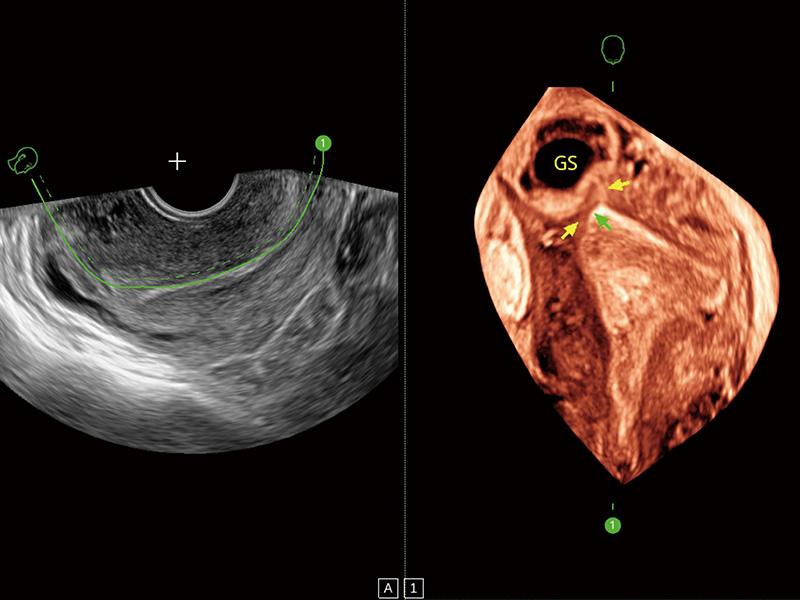

“生育问题”即关系民族复兴,也关系亿万家庭的幸福。随着婚育年龄推迟、社会压力增加等因素,越来越多人群也面临着“生不出、生不好”的问题。辅助生殖作为治疗不孕不育最有效的方法之一,也逐渐成为育儿新希望。而超声检查能为生殖需求人群的初诊评估提供宝贵的信息。 P20 Elite是开立医疗匠心打造的一款生殖应用型彩超。她继承开立医疗高端极光平台,突破性地将多款新型芯片及硬件模块进行整合,均衡了高端系统性能与小巧灵动机身。P20 Elite卓越的图像质量搭载专科探头,旨在为您提供全面的辅助生殖解决方案。

P20 Elite配备了丰富的生殖探头群和临床应用功能,在卵泡监测、穿刺取卵、胚胎移植、妊娠确认等领域,为生殖需求人群提供了新的临床机会,重新定义高端超声如何应用于生殖健康检查。